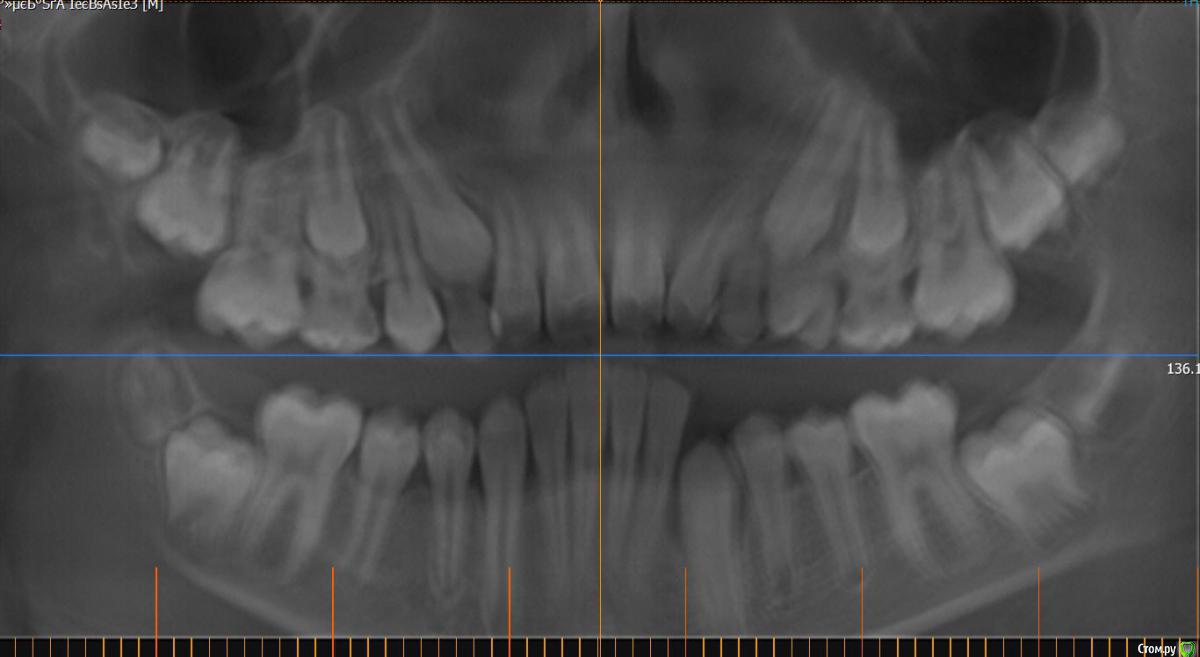

Monkey Опубликовано 27 апреля, 2016 Поделиться Опубликовано 27 апреля, 2016 (изменено) Коллеги! Прощу совета и помощи. Кто как справляется с выраженным 2-1. Парнишке 12 лет. Со слов мамы ни вредных привычек, ни родовой травмы не было. Опять же со слов мамы, есть серьезное искривление перегородки носа ( ЛОР сказал можно править только после 17 лет).Сейчас удалили зачатки 38,48. Ждем когда созреют 18,28.Как вести таких пациентов? и реально ли обойтись без хирургии? Когда начинать лечение и на каком аппарате?P.s. если у кого-то были похожие вылеченные случаи, буду благодарна за демонстрацию. Изменено 27 апреля, 2016 пользователем Monkey Ссылка на комментарий

Yana guapa Опубликовано 27 апреля, 2016 Поделиться Опубликовано 27 апреля, 2016 почему клкт делали с открытым ртом? в итоге проекции , которые вы выложили - не информативны. лучше "классика" - снимки (трг) , фото (причем полноценный набор:фас, профиль, профиль с улыбкой, обнажение резцов в покое...) это все имеет значение при составлении плана лечения и выбора методики. Ссылка на комментарий

Monkey Опубликовано 28 апреля, 2016 Автор Поделиться Опубликовано 28 апреля, 2016 почему клкт делали с открытым ртом? в итоге проекции , которые вы выложили - не информативны. лучше "классика" - снимки (трг) , фото (причем полноценный набор:фас, профиль, профиль с улыбкой, обнажение резцов в покое...) это все имеет значение при составлении плана лечения и выбора методики. Проблема в том, что ничего и нет. На консультации сказала маме, что надо ждать созревания и прорезывания зубов. но потом еще раз КТ посмотрела и решила, что надо действовать сейчас! Буду вызывать на модели и снимки. Ссылка на комментарий